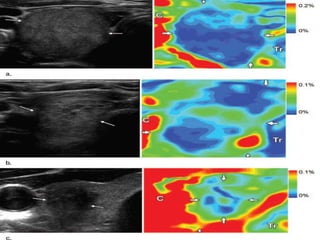

Example of selecting region of interest (ROI) to compute thyroid stiffness index

within a nodule.

(a) Transverse US image showing a nodule (arrows) within thyroid gland (Tg),

the trachea (Tr), and the carotid artery (C).

(b) Combined US image and elastogram of this nodule; average strain of

stiffest region inside a thyroid nodule (ROI #1) is used as denominator of

thyroid stiffness index.

(c) Combined US image and elastogram of this nodule with a different scale to

better visualize the areas of highest strain near the carotid artery. Average

strain of the highest-strain regions near the carotid artery (ROI #2, ROI #3) is

used as numerator of thyroid stiffness index. Range of the color map is

adjusted to better visualize ROIs.